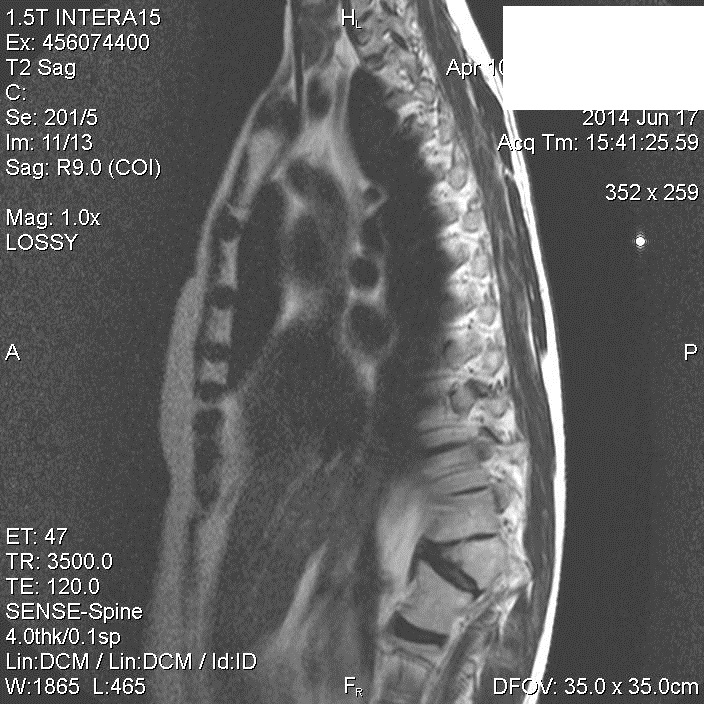

Хороший букет аномалий. Конкресценция, клиновидный (бабочковидный) позвонок, незаращение остистых отростков (spina bifida) ничего не забыл?